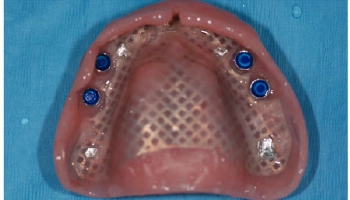

4 Implant Retained Maxillary Denture

Before image of a maxillary denture, showing missing teeth. After image of a maxillary denture supported by four implants. Before and after images of a maxillary denture with implants.